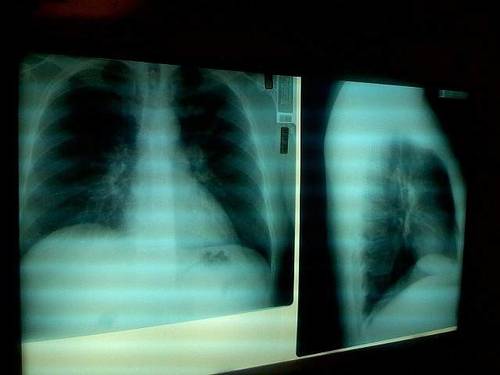

El consumo de analgésicos opiáceos aumenta un 30 por ciento el riesgo de neumonía en personas con enfermedad de Alzheimer, según muestra un estudio reciente de la Universidad de Finlandia Oriental. Según sus hallazgos, publicados en la revista 'Journal of Alzheimer's Disease', este riesgo fue más pronunciado en los dos primeros meses de uso.

La incidencia de la neumonía fue mayor entre los que utilizaban opiáceos fuertes, como oxicodona o fentanilo, pero también se incrementó entre los que utilizaban buprenorfina, tramadol o codeína. Las personas con cáncer fueron excluidas del estudio, y otras enfermedades y el uso de drogas se tuvieron en cuenta en los análisis. Los investigadores puntualizan que los opiáceos perjudican la tos y las funciones respiratorias y causan sedación, lo que posiblemente subyace al mayor riesgo de neumonía.

La neumonía es una complicación grave pero relativamente frecuente entre las personas con enfermedad de Alzheimer, y a menudo conduce a la hospitalización e incluso a la muerte. Los opiáceos son importantes en el tratamiento del dolor agudo severo, pero el tratamiento debe iniciarse en dosis bajas y evaluarse regularmente tanto en términos de beneficios como de daños.